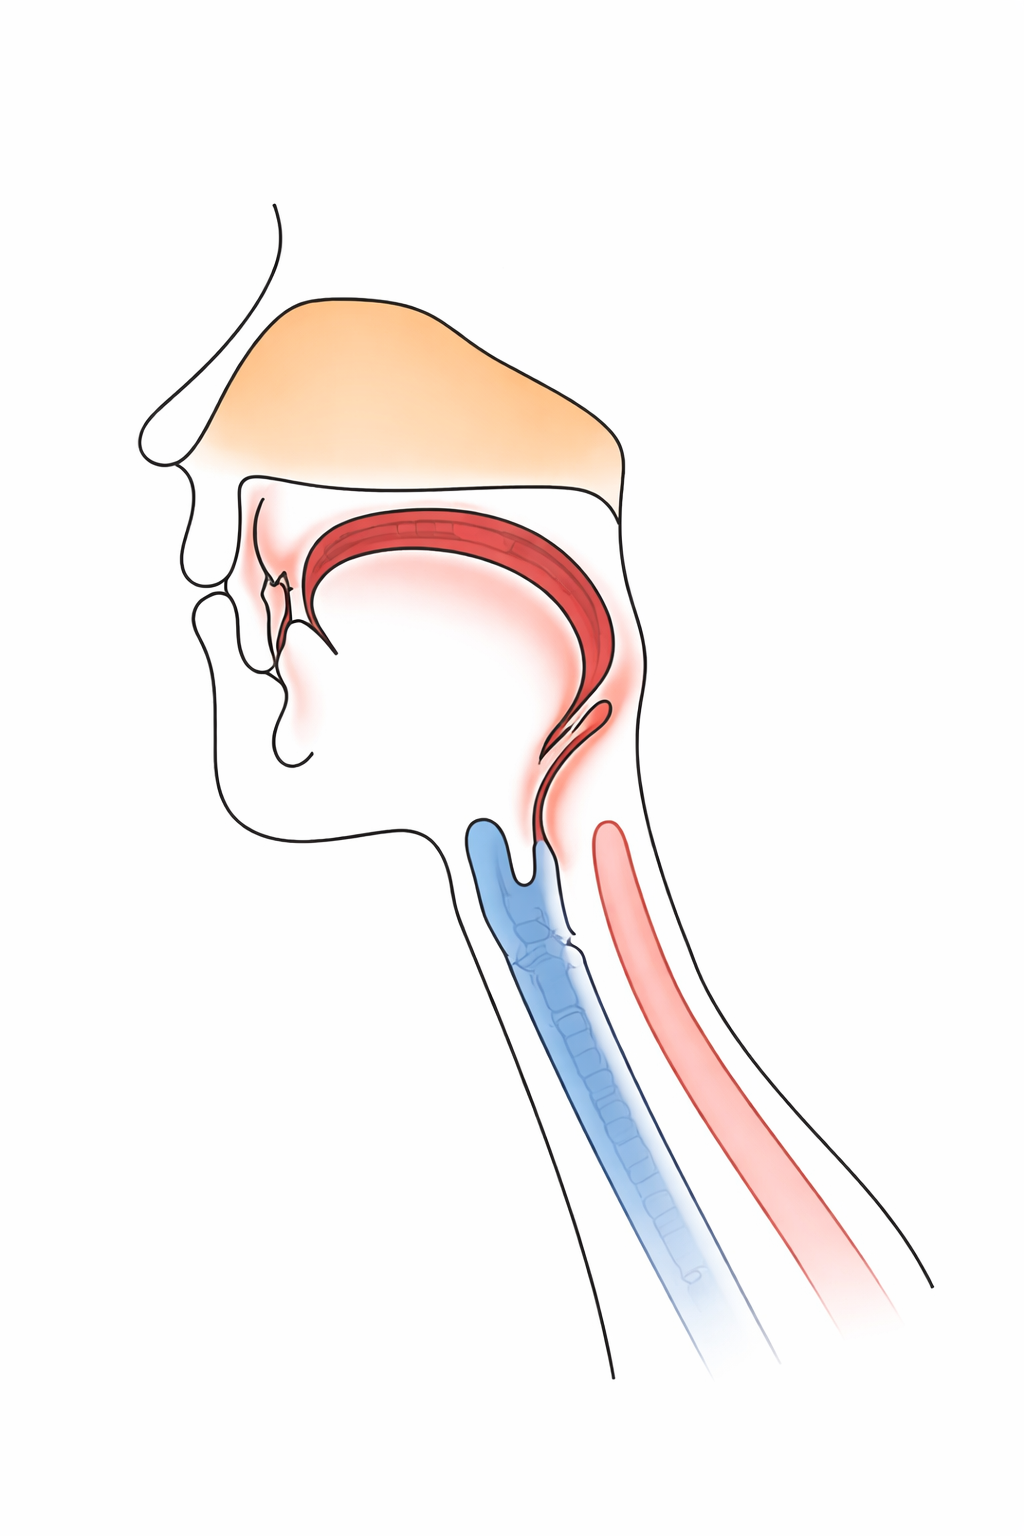

舌接触補助床(PAP)とは,手術やけがなどで舌(した)の一部がなくなった方や,脳梗塞などの病気で舌の動きが弱くなってご飯が食べられない方や,うまく言葉を話せない方のために作る,舌の動きを助けるための特別な入れ歯の一種です.上あごの入れ歯や装置の一部の厚みを増やすことで,舌と上あごの接触を良くし,咀嚼(そしゃく)や飲み込み,発音などのお口の機能の改善を図る装置です.

舌接触補助床が適用される患者さんは,主に舌や下あごの腫瘍などによって舌の一部や全てなくなった方や,脳梗塞やパーキンソン病などの飲み込みや発音に障害がみられた方になります.また,このような病歴がない方でも,舌の筋力測定(舌圧検査)で一定の基準を満たさなかった方も適用されることがあります.

舌は,食べ物を噛んで飲み込むときや,言葉を発音するときに大切な役割を担っています.しかし,舌の一部を失ったり,動きが制限されると,

・食べ物をうまくまとめられず,飲み込めない

・「サ」「タ」「ナ」「ラ」などの音が発音しにくい

・舌が上顎に届かず,言葉がはっきりしない

といった不自由が生じます.

舌接触補助床は,失われた舌の高さや届く範囲を入れ歯や装置の“厚み”を増やしたり調整したりすることで,舌が上あごに接触しやすくなるようにサポートすることで,食事や会話をより自然に行えるようにします.

舌接触補助床を装着することで,以下の機能改善が期待されます.

①食べ物をまとめやすくなり,飲み込みがスムーズになる

②言葉が明瞭になり,会話がしやすくなる

③舌の動きが自然になり,発音のストレスが減る

ただし,会話と飲み込みの際の舌の動きは異なるため,両方の機能を同時に改善することができないことがあります.その際は,食事用と会話用の2種類の舌接触補助床を製作することがあります.補綴の分野でとても大切な役割を担っています。